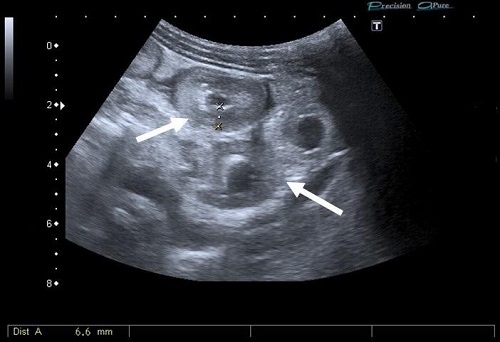

Se presenta el caso de un niño de 8 años sin antecedentes personales que acude a Urgencias con dolor abdominal de 48 horas de evolución, acompañado de vómitos y hematoquecia, siendo la analítica anodina. Tres horas después, el paciente presenta pérdida de conciencia junto a palidez intensa. Ante el cuadro clínico con persistencia del dolor abdominal, se solicitó ecografía abdominal, donde se visualizó engrosamiento de pared de las asas intestinales, ausencia de peristaltismo, hiperecogenicidad de la grasa y abundante ascitis (Fig. 1). Se identificaron arteria hepática, vena cava inferior y venas suprahepáticas permeables, no observando flujo en la vena porta, en el hilio hepático ni en las ramas intrahepáticas. Por ello, se decidió completar el estudio con tomografía computarizada (TC) con contraste intravenoso en fases arterial, portal y tardía, confirmando trombosis de vena porta con extensión a eje esplenomesentérico, infarto esplénico y ausencia de realce de asas intestinales en relación con proceso isquémico (Fig. 2).

| Figura 2. Imagen de TC abdominopélvica con contraste intravenoso en fase portal, corte axial, donde se identifica ausencia de repleción de la vena porta y sus ramas (flecha fina) compatible con trombosis. Además, se aprecia ausencia de realce de la práctica totalidad del parénquima esplénico, sugerente de infarto esplénico venoso (flecha hueca). Se observan asas intestinales en compartimento supramesocólico con ausencia de realce tras la administración de contraste intravenoso, sugerente de proceso isquémico de etiología venosa (cabeza de flecha). |